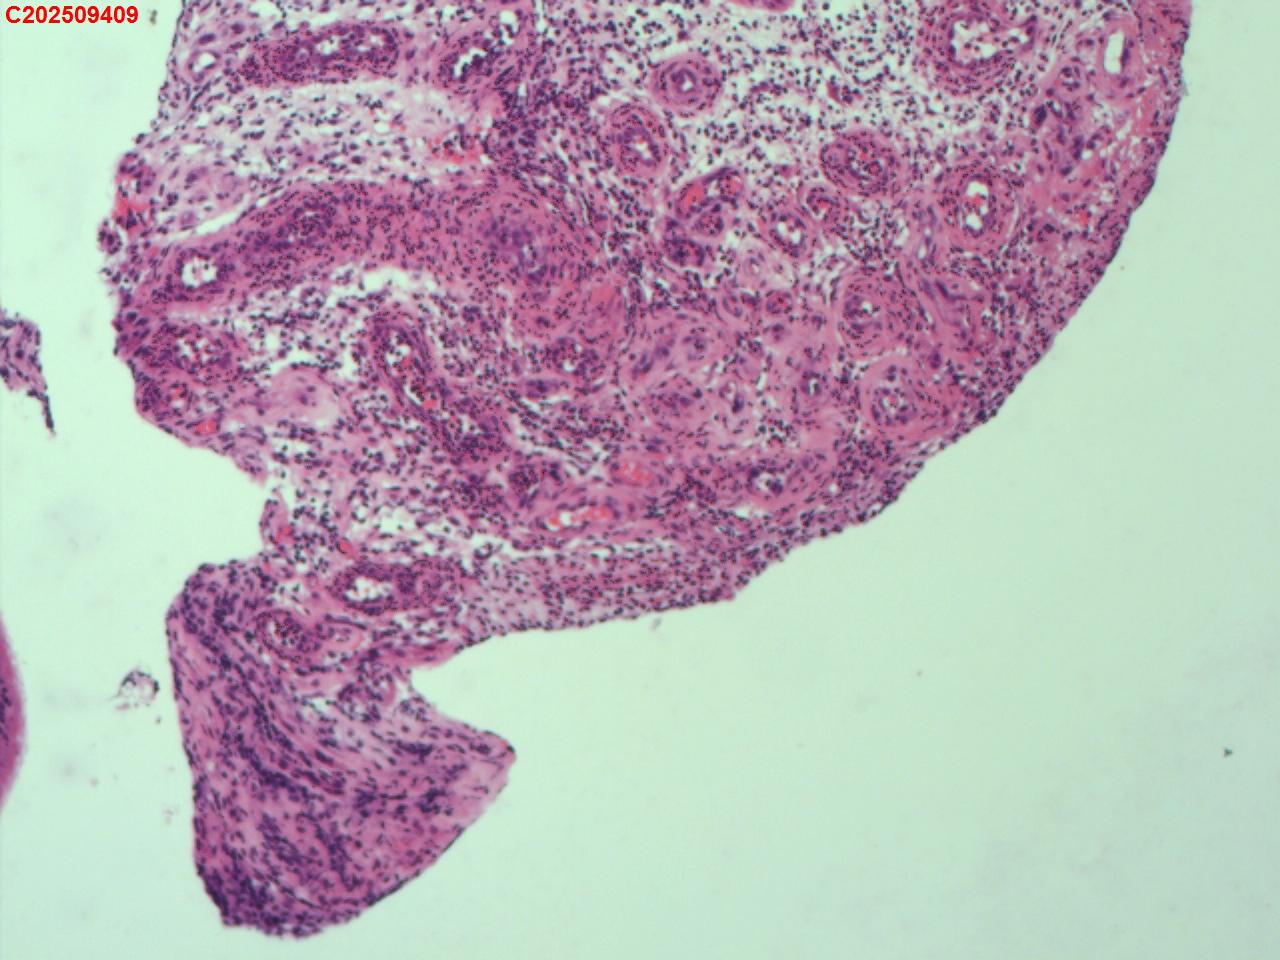

性别年龄62岁临床诊断社区获得性肺炎,肺占位性病变带除外

一般病史胸部CT:双肺可见多发斑片状、结节状高密度影,右肺上叶及左肺下叶病灶内见多发空洞,右侧少量胸腔积液。

标本名称纤支镜咬检

大体所见纤支镜:气管通畅,隆突锐利。右肺主支气管通畅,右肺上叶见少量痰液,负压吸引后见上叶开口干酪坏死物质附着,上叶各段级支气管通畅未见新生物及坏死物质,中叶、下叶背段支气管通畅,下叶基底段见新生物阻塞气道,粘膜无充血。左肺主支气管、上叶、下叶及各段级支气管通畅,粘膜无充血,未见新生物及坏死物。

考虑:支气管炎性息肉